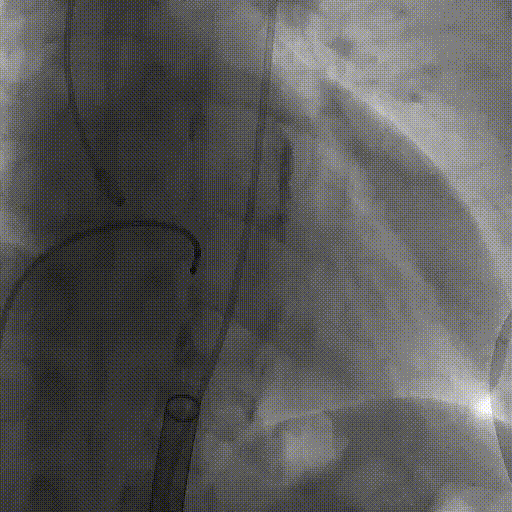

造影提示主动脉瓣大量反流